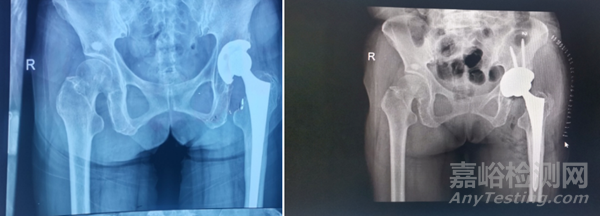

左圖:術前髖臼內襯磨損             右圖:髖關節翻修術

這里特別說一下髖關節表面置換術,它使用金屬假體置換股骨頭,其中金屬髖臼組件的作用就是建立一個金屬與金屬的承載面,承載面的反應與質量會限制它的應用,例如會出現假體磨損、感染、松動等情況。

根據澳大利亞相關數據表明,表面置換術后的5年累積翻修率顯著上升,如何提高材料的抗疲勞度呢?